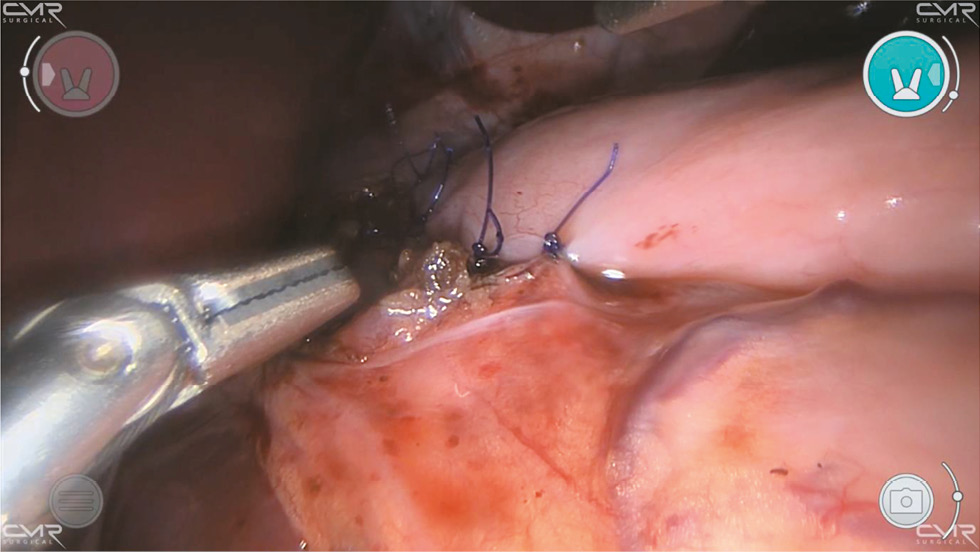

После адекватной миотомии через назогастральный зонд выполняют аэропробу с инсуффляцией воздуха для проверки герметичности слизистой оболочки. Кончик зонда в это время находится в пищеводе над местом хирургического вмешательства. Затем дно желудка перемещают к разрезу пищевода и выполняют частичную переднюю фундопликацию по Дору путём подшивания дна желудка к краям миотомии нитями PDS II 2–0 (рис. 3, рис. 4).

Рис. 3. Роботизированная миотомия Хеллера: этап фундопликации по Дору (фиксация латерального края манжеты).

Fig. 3. Heller robot-assisted myotomy: Dor fundoplication stage (fixation of the lateral edge of the cuff).